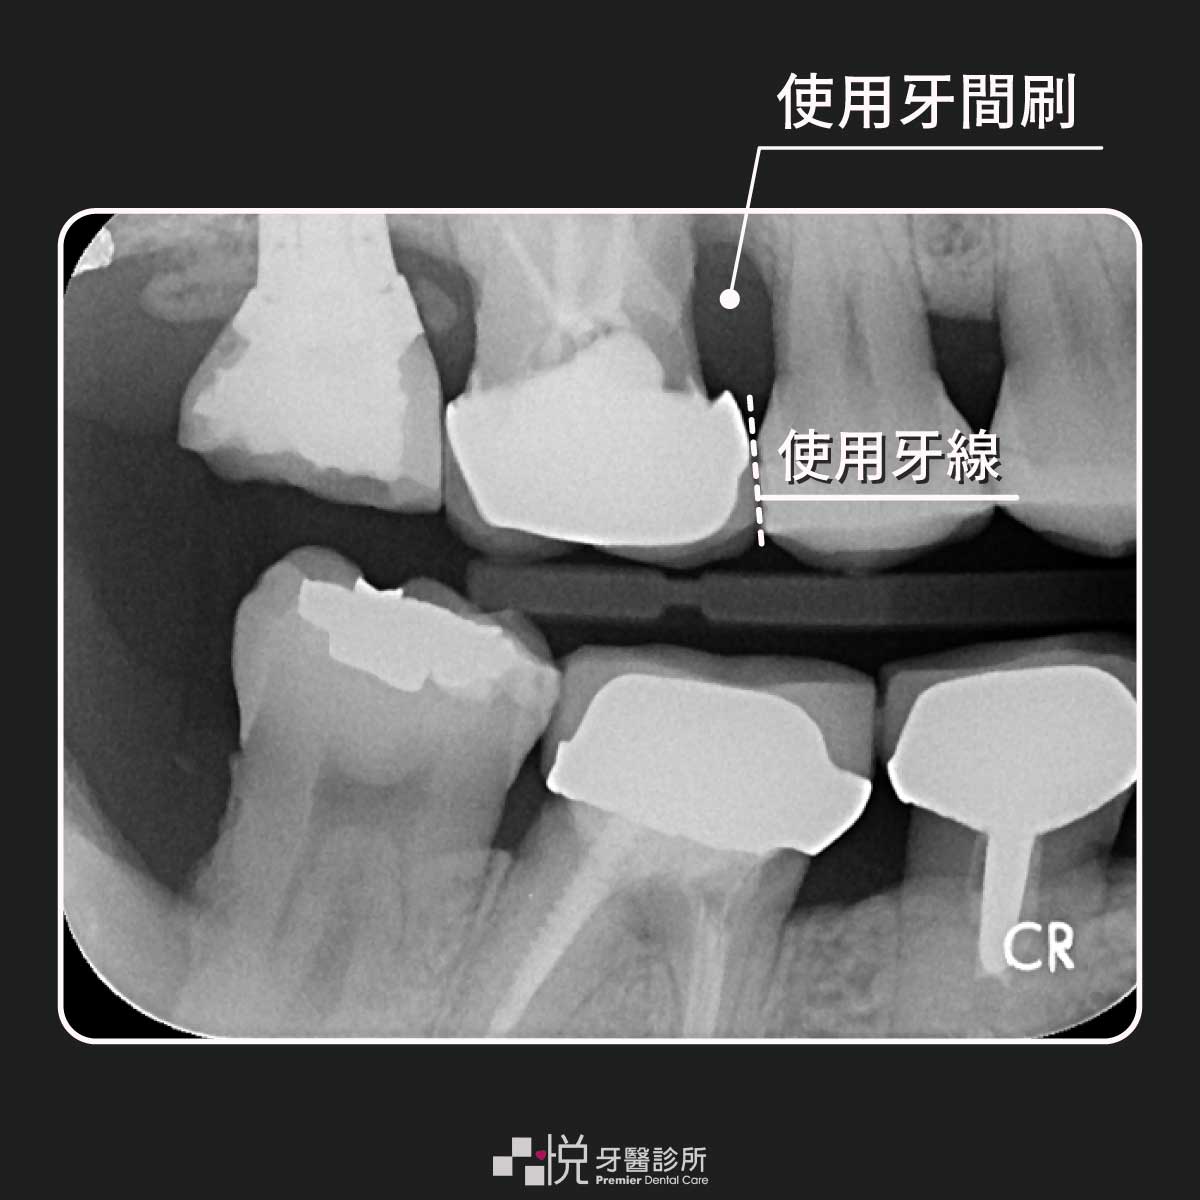

2. 牙間刷:

多半有牙周病的病患,通常牙周病比較嚴重的地方大部分都是牙齒跟牙齒的接觸處,也就是除了刷牙以外沒特別注意牙齒接觸處的清潔所致。

如果有牙周病的病人牙齒接觸面的清潔首選是牙間刷喔!

3. 牙線:

有牙周病的病人,牙齒接觸面需用牙間刷清潔,那牙線用在何時?

簡單的原則為最小號的牙間刷都放不進去的地方(如齒列擁擠),就是要用牙線的時候啦~

另外在預防蛀牙的觀點來看,即使牙間刷可以放的進去,但牙線也會建議一起用喔!牙間刷不要沾牙膏喔,但是每刷完一個縫隙可以用清水沖一下。